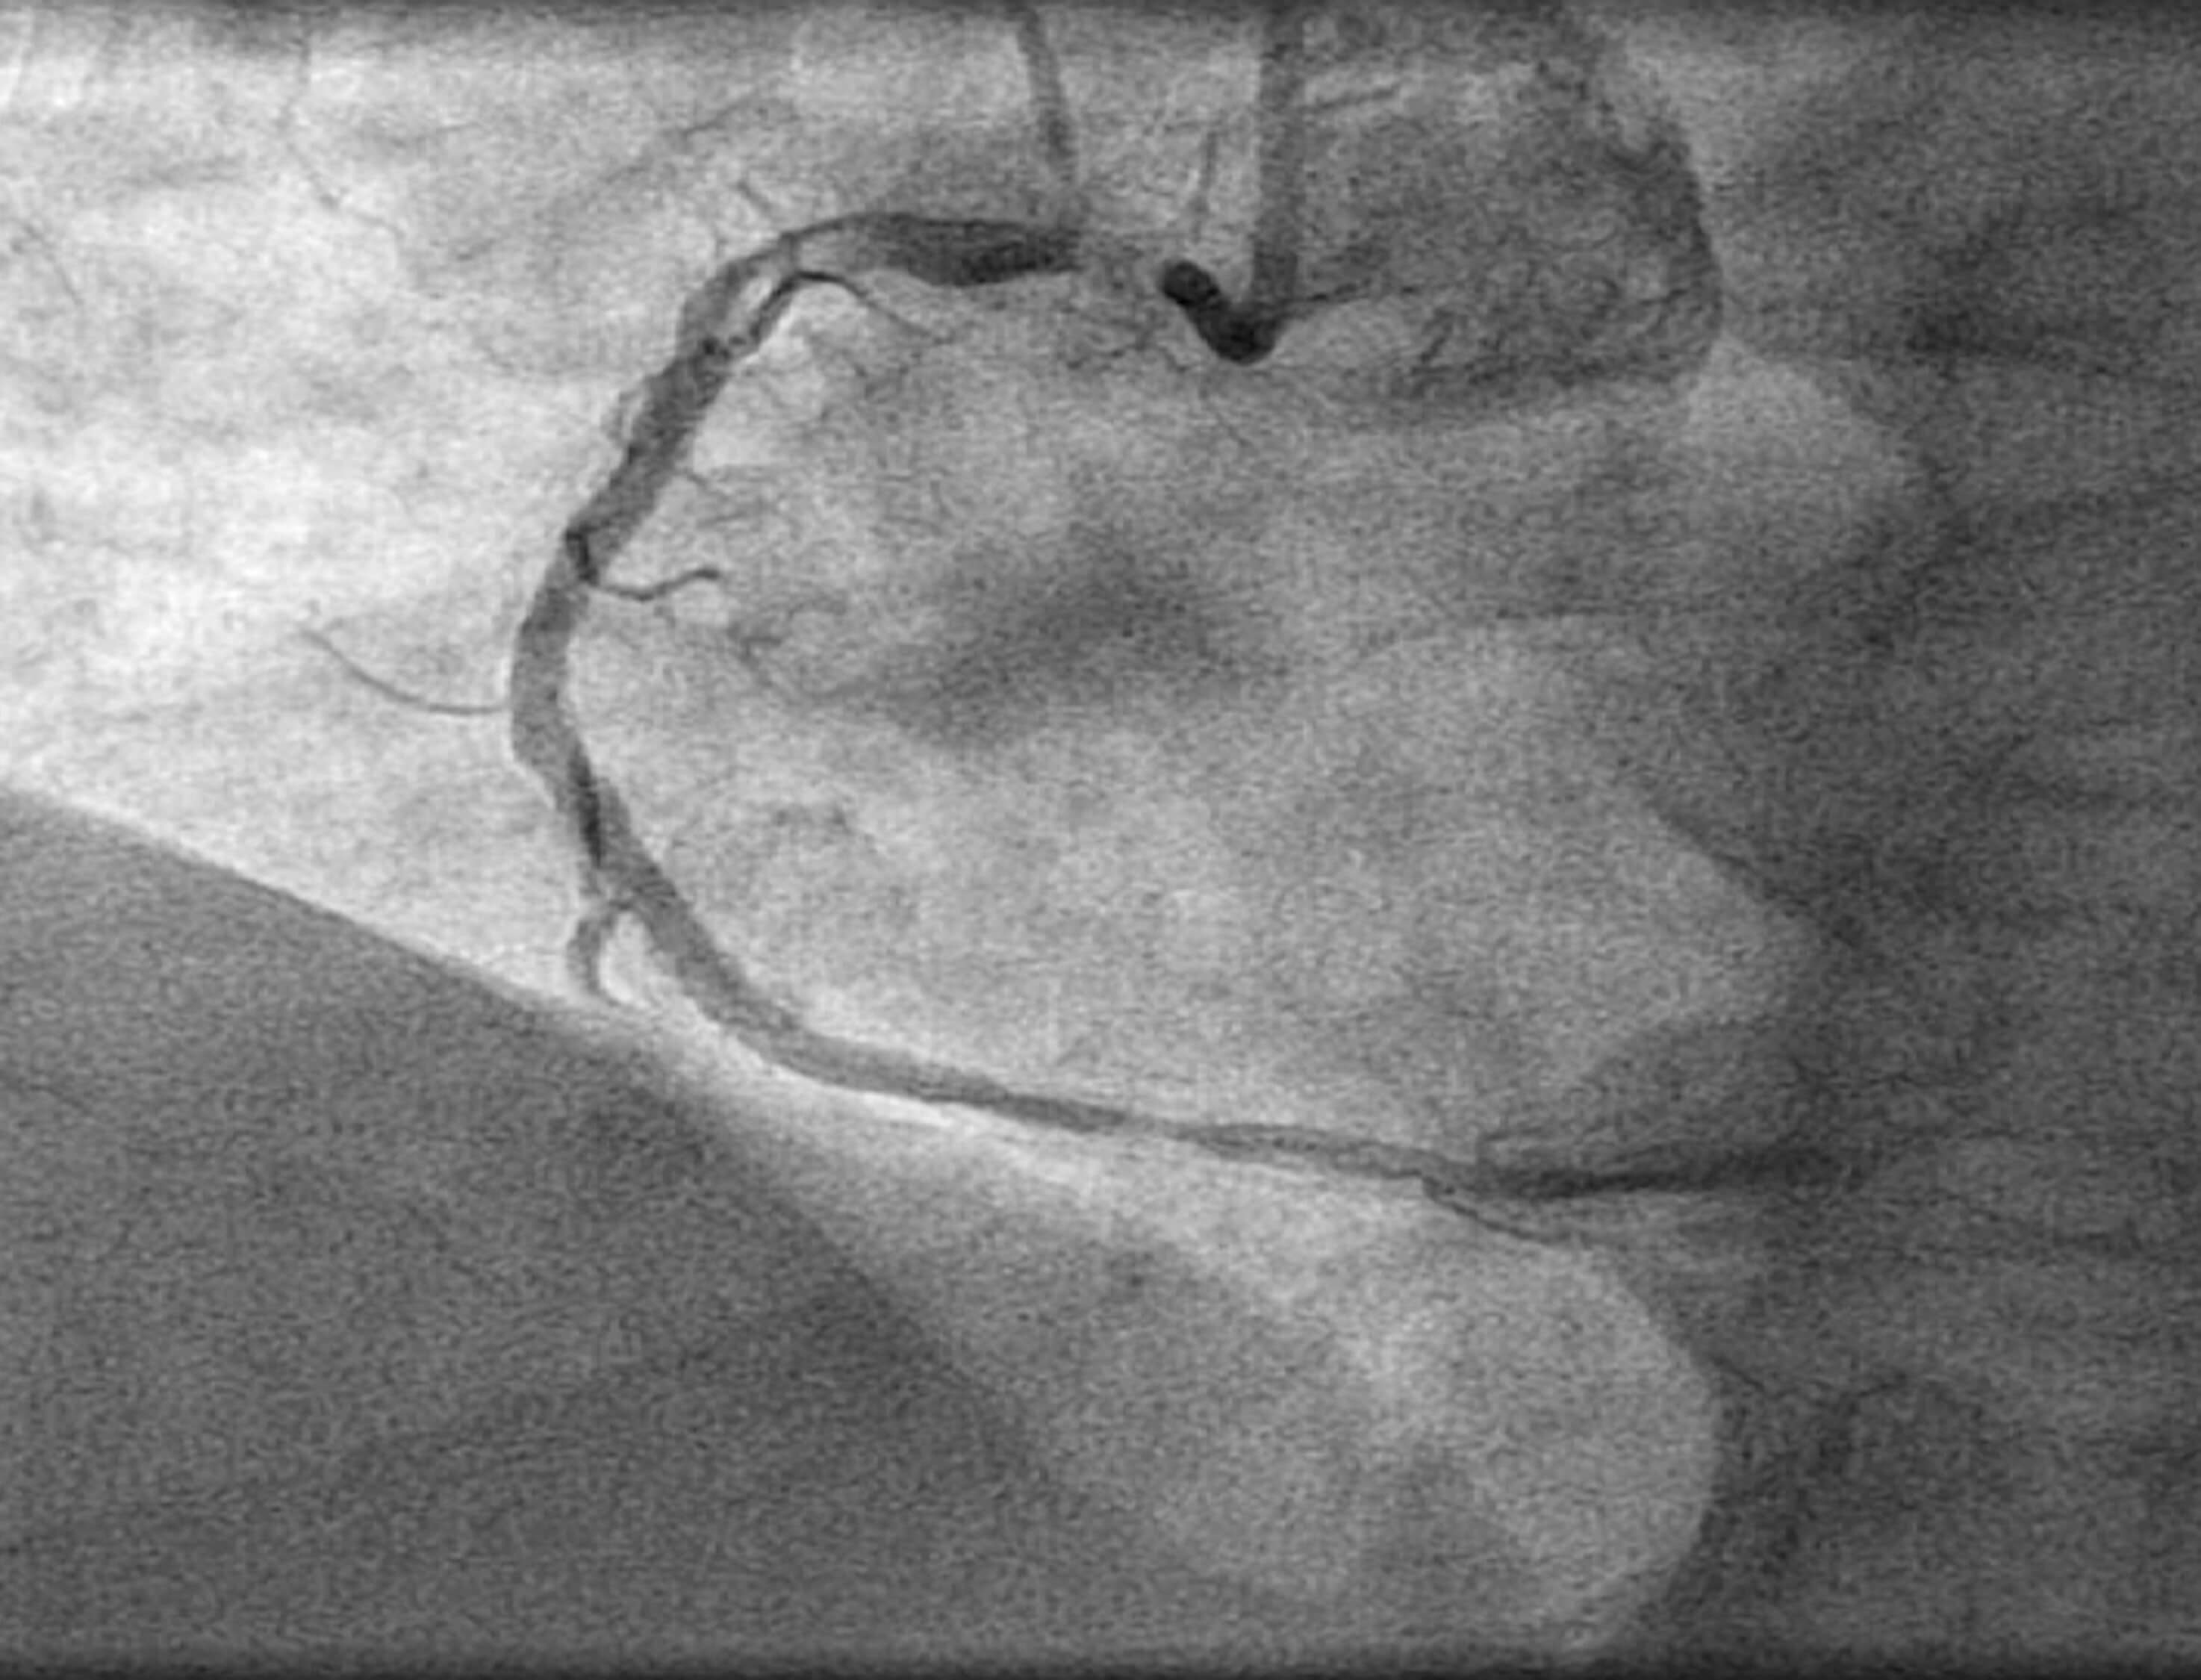

En la coronariografía diagnóstica realizada por vía radial derecha destacó la presencia de una placa complicada con trombo en el ostium de la arteria coronaria derecha con flujo Thrombolysis in Myocardial Infarction 3 (figura 1).

Figura 1. Lesión de aspecto complicada aguda en el ostium de la arteria coronaria derecha.